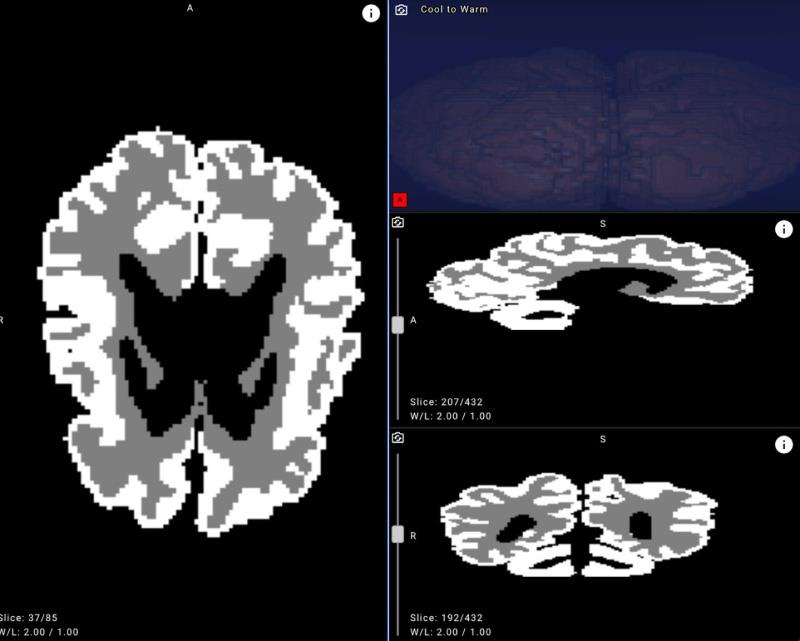

Example of an MRI brain image with white matter and gray matter masks applied after neural network processing.

To bridge this gap, Yandex researchers collaborated with medical experts to create new annotations, design a dedicated neural network architecture, and run a series of machine learning experiments. The resulting model achieved over 90% accuracy in distinguishing gray and white matter in infant brains on internal evaluation data, demonstrating its potential for clinical use.